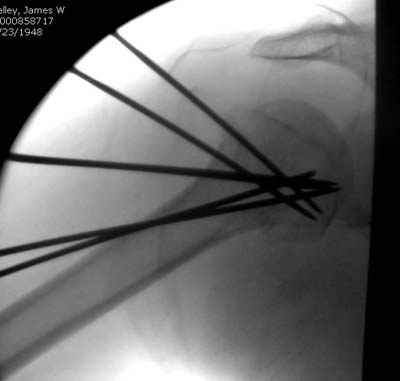

Как я видел в ЦИТО, используется инструмент-направитель типа зажима с браншами в виде разъемной трубки, наподобие тех, что ЛОРы суют в нос и ухо.

Да. У нас довольно скромный опыт такого остеосинтеза (по 2 случая - плечо и наружная лодыжка), дошли до использования самого простецкого троакара, через который мы сверлим кость и вводим 6 мм стержни, когда накладываем аппарат. Соответственно, в качестве забойника отлично работает любой стержень от аппарата Илизарова. Еще из наших туземных особенностей - страшная любовь к спицевым дистракторам, поэтому делали в нем. Результат у этой дамы неизвестен, т.к. она из области и уехала рожать сразу после остеосинтеза, сейчас прошло больше 5 месяцев...

Что-то, наверно, сделали мы не совсем оптимально, поскольку у Анатолия Федровича и его соратников как-то красивее "раскрываются" спицы в головке плеча - надеюсь, он прокомментирует и подскажет, что надо подправить.